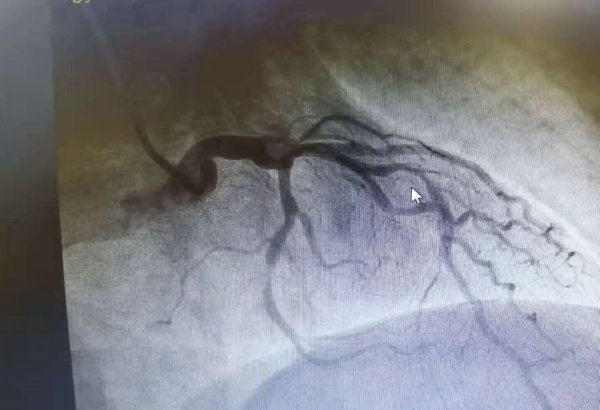

术前狭窄血管

40多岁的王先生,因心绞痛入住心血管内科五病区。冠脉造影提示前降支中段严重狭窄,需支架植入解除狭窄病变,改善心肌供血,降低心梗、猝死等风险。梁主任带领心血管内科五病区团队一起仔细分析了患者的病情,考虑患者为中年男性,使用传统药物涂层金属支架,再狭窄率会逐年增加,为了给王先生在心脏冠脉介入治疗中有更好的选择,梁主任认为该患者严重狭窄的血管适合植入可吸收支架。